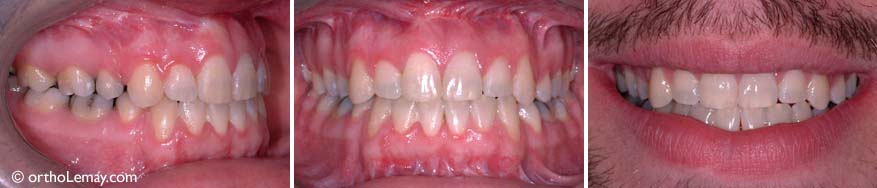

(A) Sévère malocclusion de type Classe III avec constriction maxillaire, occlusion croisée et béance postérieure bilatérales et manque d’espace important. (B) La déficience maxillaire (constriction et recul du maxillaire supérieur) se reflète dans le recul de la lèvre supérieure. (C) Occlusion à la fin du traitement. Un avancement maxillaire chirurgical fut nécessaire pour avancer la mâchoire supérieure et améliorer le profil. Aucune extraction ne fut nécessaire et aucun appareil d’expansion ne fut utilisé. (D) Le résultat final montre une lèvre supérieure plus avancée et un profil plus équilibré.